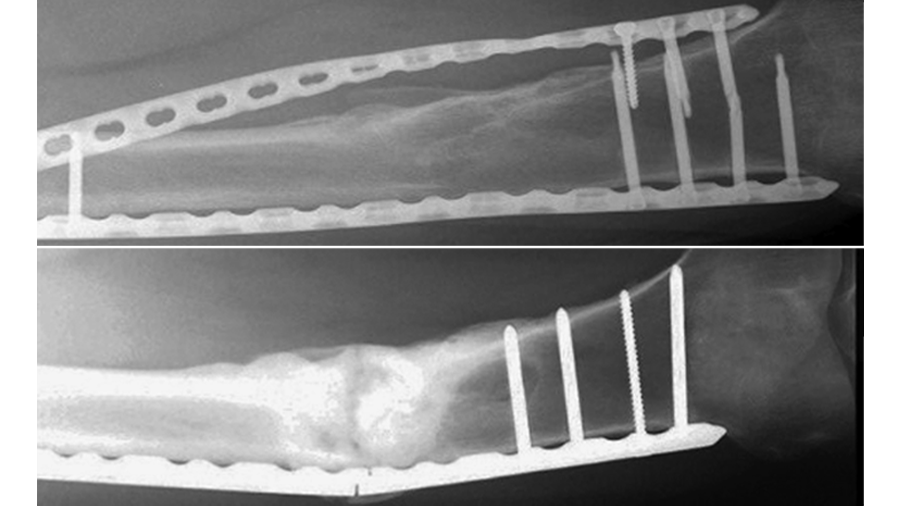

Eight pairs of human anatomical specimens, namely lower legs, were scanned by computed tomography (CT) under 700 N single-leg axial loading in five foot positions – neutral, 15° external/internal rotation and 20° dorsiflexion/plantarflexion in three different states: (1) pre-injury (intact); (2) injured, characterized by complete syndesmosis and deltoid ligaments cuts simulating pronation-eversion injury types III and IV as well as supination-eversion injury type IV according to Lauge-Hansen; (3) reconstructed, using a screw-suture (FIBULINK, Group 1) or a suture-button (TightRope, Group 2) implant for syndesmotic stabilization, placed 20 mm proximal to the tibia plafond/joint surface (Fig 2).

Next, all specimens were biomechanically tested over 5000 cycles under combined 1400 N axial and ±15° torsional loading. Clear space (diastasis), anterior tibiofibular distance, talar dome angle, and fibular shortening were measured radiologically from the CT scans. Anteroposterior, axial, mediolateral, and torsional movements at the distal tibiofibular joint level were evaluated biomechanically via motion tracking.